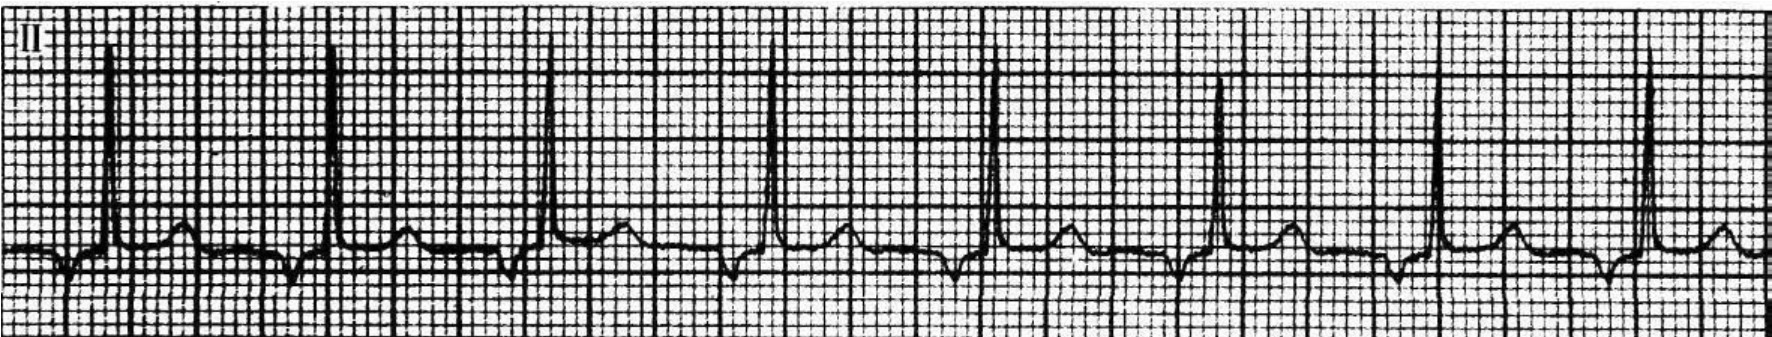

图44-19 加速的房性逸搏心律(起源于心房下部,其P--R间期0.14s,频率9 2次/min)